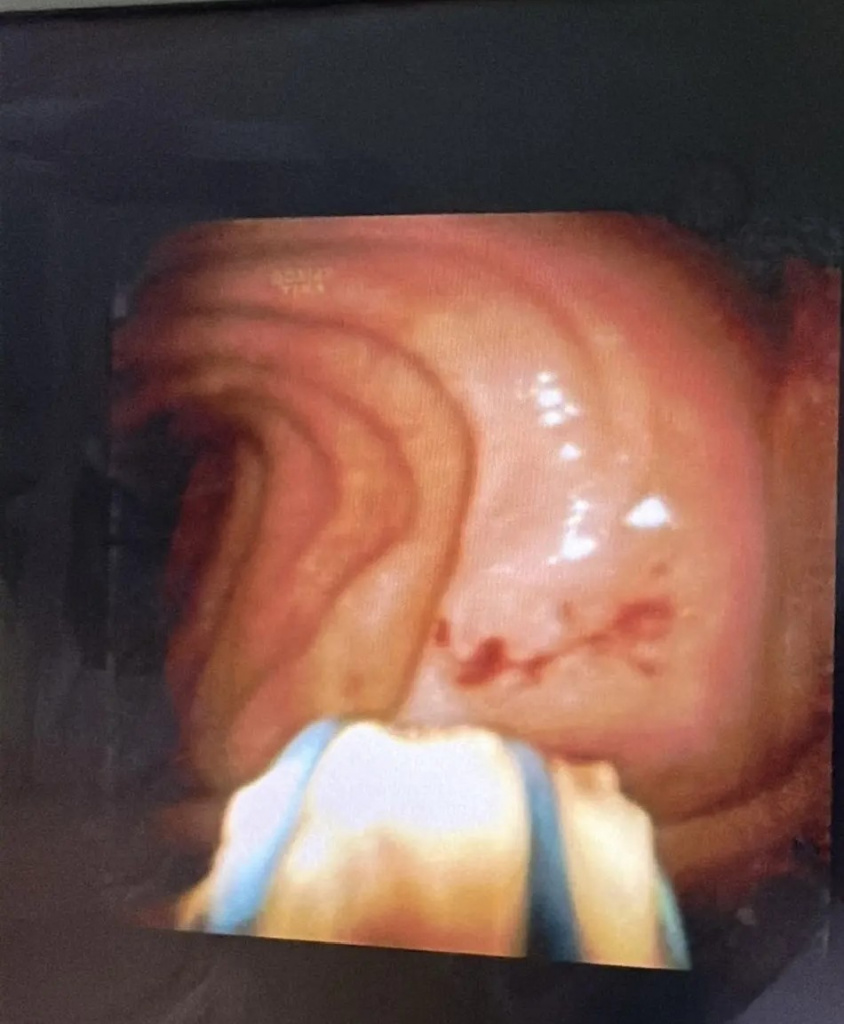

Операция выполняется доступом из ротовой полости без разреза, сразу после осмотра желудка и двенадцатиперстной кишки, через естественное отверстие для оттока желчи и панкреатического сока. Ход вмешательства контролируется двумя видеокамерами, со стороны просвета желудочно-кишечного тракта и дополнительной миниатурной видеокамерой внутри просвета протоковой системы поджелудочной железы.

При этом электро-гидравлическое воздействие разрушает камни на более мелкие фрагменты, которые затем могут быть удалены специальными эндоскопическими инструментами.